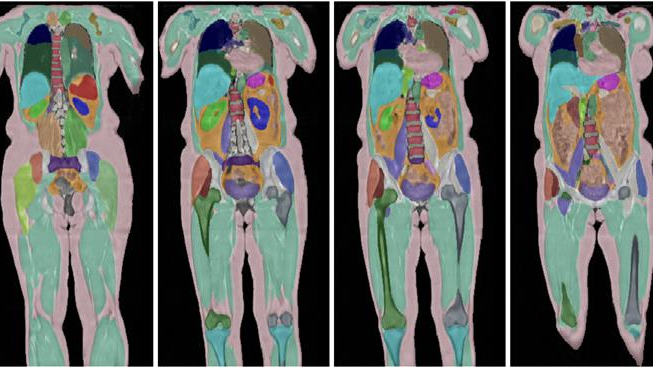

The UK Biobank has reached a significant milestone in its groundbreaking human imaging study, having scanned the bodies of 100,000 volunteers. This ambitious project, which began in 2014, aims to revolutionize the way diseases are detected and treated by providing researchers with unprecedented insights into the human body.

The imaging study, part of the larger UK Biobank initiative, has generated over a billion detailed images of participants' brains, hearts, and other organs. These images, combined with extensive health and lifestyle data, are expected to transform our understanding of the ageing process and the early signs of disease. "Researchers now have an incredible window into the body," said Prof Naomi Allen, chief scientist at UK Biobank. "For the first time, researchers can study how we age and how diseases develop in stunning detail and at a massive scale."